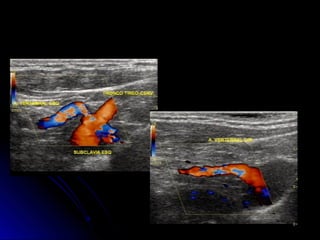

TortuosidadesTortuosidades